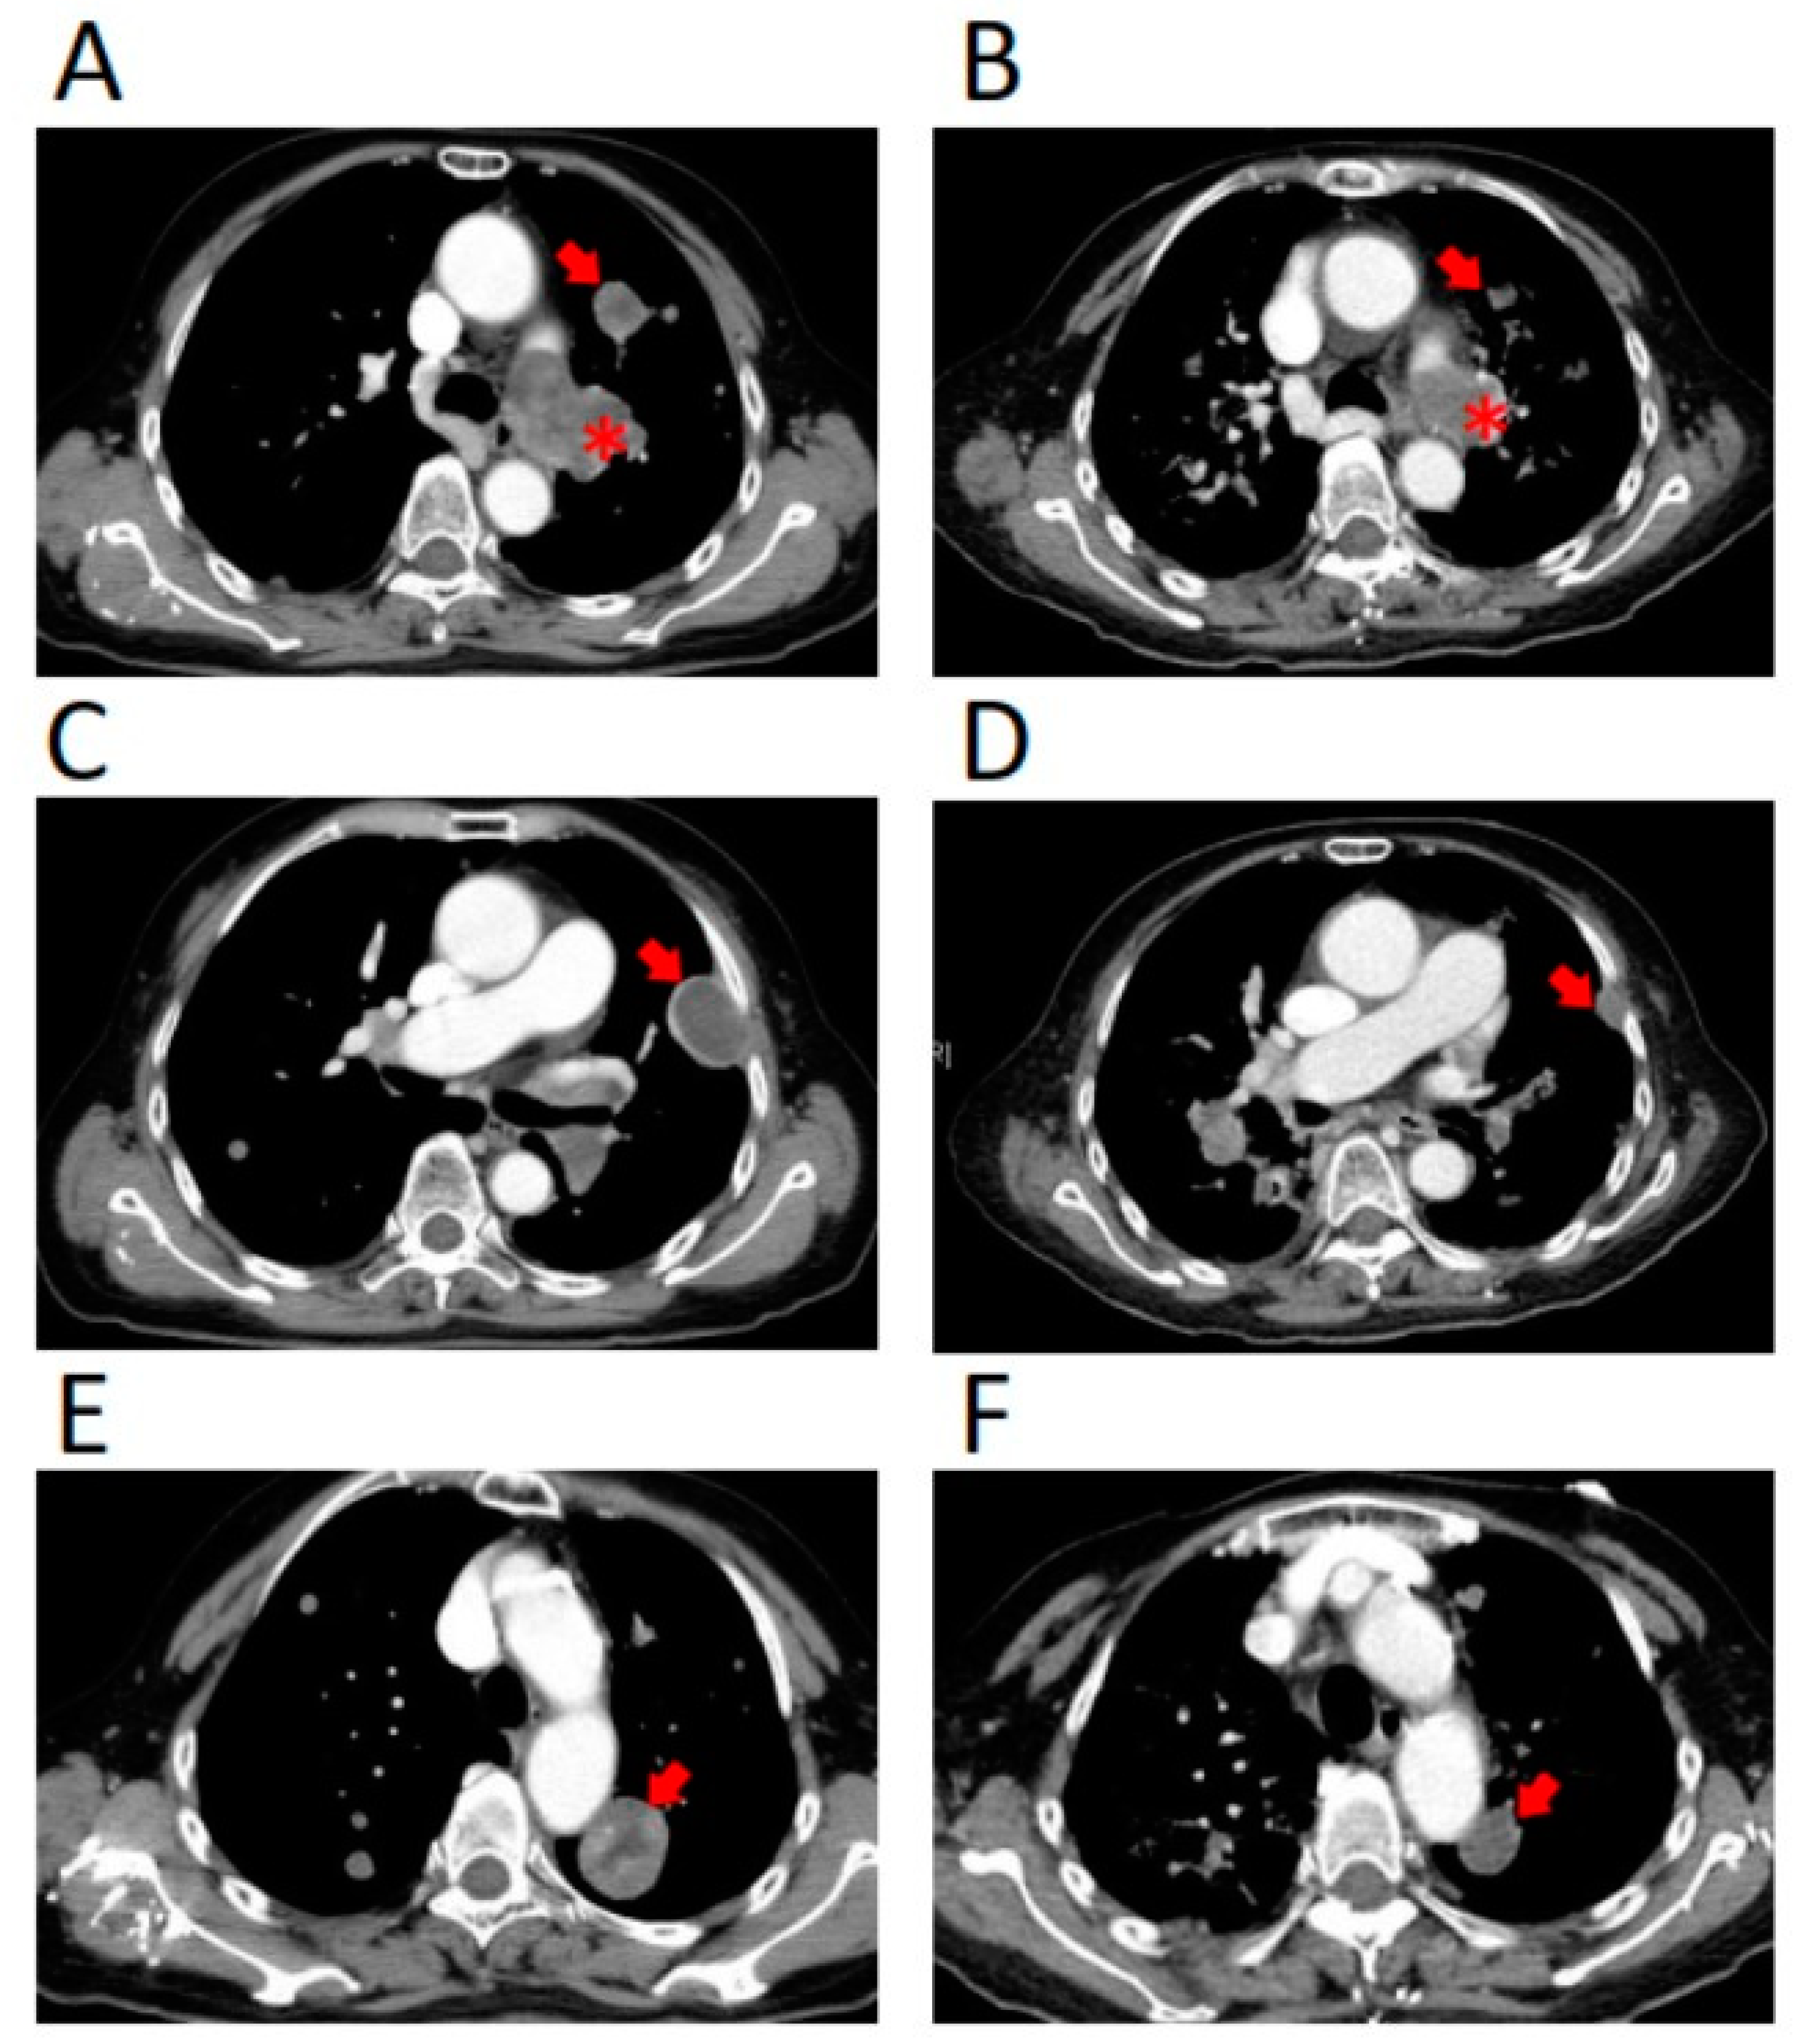

2. Case Report

3. Treatment Course